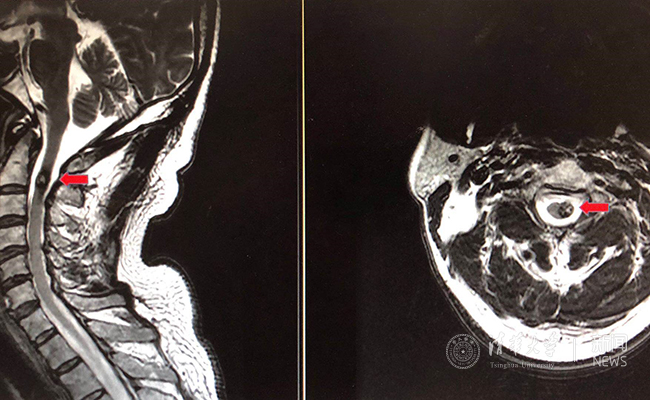

徐先生术前磁共振成像(MRI)影像,红色箭头所指为血管瘤

徐先生采取了观察和定期随访的方式,每两年做一次磁共振成像。但2017年11月之后,他感到症状发展的速度明显加快,整个后背放射性疼痛,左手臂也开始麻木、间歇性地抽搐,而且间隔时间越来越短。医生提醒徐先生,他的血管瘤有破裂的风险,一旦破裂,可能引发大出血甚至休克。“我们每天都提心吊胆,生怕出事。”徐先生的妻子说。血管瘤像是随时可能破坏他们生活的定时炸弹,面对越来越严重的症状,两人终于下定决心,进行手术治疗。